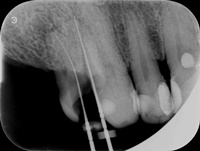

Pacjentka zgłosiła się z bólem. Ząb prawa dolna czwórka po leczeniu kanałowym. Nawracające dolegliwości bólowe, od kilku lat okresowo zaostrzające się. Podjęto decyzję o rewizji leczenia kanałowego. Udróżniono kanał korzeniowy, oraz odnaleziono kanał dodatkowy. Zdjęcie początkowe i zdjęcie po leczeniu endodontycznym pod mikroskopem.